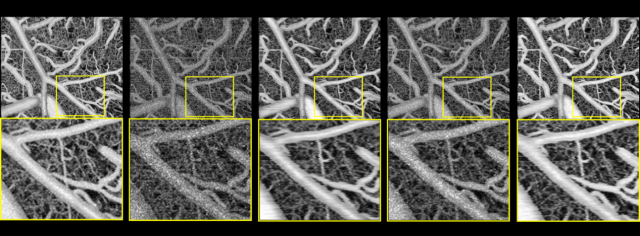

研究团队分别利用SD大鼠脑部血管造影数据和健康人眼数据对弱监督深度学习OCTA重建算法框架进行验证。提出的弱监督学习模型在SD大鼠数据集上展示了足以媲美基于高质量标签的监督学习算法的重建质量。不论是在噪声水平、对比度还是血管连续性上,均要明显好于目前最好的解析算法SSAPGA及基于低质量标签的监督学习算法,展现出良好的图像对比度和低散斑噪声水平。进一步,研究团队在人眼数据集上印证了在动物实验数据上得到的结论。这使得提出的弱监督学习算法具备了很好的临床应用前景。

图2. 弱监督深度学习OCTA重建算法及对照方法在SD大鼠数据上的重建结果

图3. 弱监督深度学习OCTA重建算法及对照方法在人眼数据上的重建结果